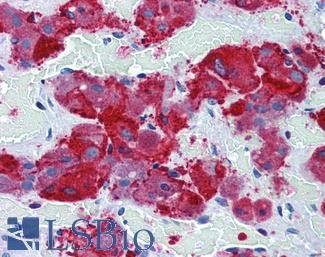

ERBB2 / HER2

Anti-ERBB2 / HER2 antibody IHC of human breast, carcinoma. Immunohistochemistry of formalin-fixed, paraffin-embedded tissue after heat-induced antigen retrieval. Antibody LS-B2133 concentration 5 ug/ml.